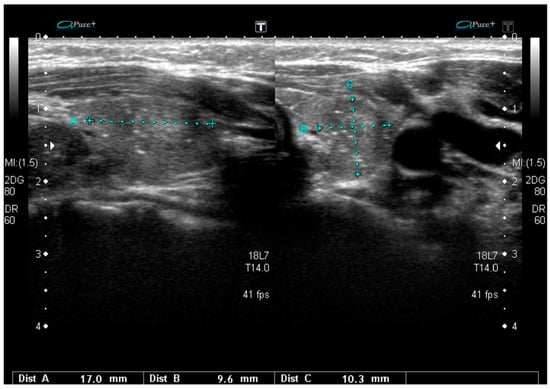

RET/PTC rearrangements are the second most common genetic alteration in PTC, mainly being a genetic driver of the classic variant. More rarely, it can be associated with other variants of PTC, especially with the diffuse sclerosing variant (DSV) [,]. The two most common types of rearrangements in PTC are paracentric inversions, RET/PTC1 and RET/PTC3. The prevalence of RET/PTC rearrangements in PTC is 6% to 30%, and they occur more commonly after radiation exposure and/or in children [,]. Data on the correlation between this genetic alteration and US patterns of PTC are very scarce and frequently inconsistent [,,,]. Isoechogenicity was described as being more common than hypoechogenicity in nodules with RET/PTC3 rearrangement []. Microcalcifications are present in the majority of cases [,]. Additionally, small-sized noduled and lymph node metastases are also typical in US []. RET/PTC rearrangement is the most common genetic feature in DSV [,]. The diffuse sclerosing variant frequently occurs in young women []. Despite having a similar genetic landscape, the US patterns of DSVs and classic variants are entirely different. Characteristic features of DSV include diffuse involvement of one or both thyroid lobes (frequently, no single separated tumor nodule is present), with heterogeneous parenchyma, ill-defined margins, solid hypoechoic nodules (if it is possible to separate any nodule), and scattered microcalcifications within or without the defined nodule (a “snowstorm” pattern). Additionally, lateral nodal involvement with typical nodal microcalcifications is often found []. This variant may sometimes resemble chronic thyroiditis. In cytology, extensive squamous metaplasia, numerous psammoma bodies, dense lymphocytic infiltration, and stromal fibrosis are typically described. The US pattern of DSV harboring RET/PTC rearrangements seems to be different in RET/PTC1- and RET/PTC3-positive cancers. Typical diffuse involvement with scattered microcalcifications without any visible nodule is much more frequent in RET/PTC3-driven tumors. The coexistence of DSV and Hashimoto’s thyroiditis is characteristic for RET/PTC1 mutations. In these last cases, microcalcifications are less frequent than in RET/PTC3 tumors []. BRAFV600E mutations are rare (24%) in DSVs [] and the sonographic pattern of such tumors is quite similar to those that harbor RET/PTC1 fusions and are significantly different from those with RET/PTC3 rearrangement. In US, BRAFV600E-positive DSVs are more similar to other PTCs that harbor BRAFV600E than a typical DSV pattern, as the nodules are usually clearly visible and diffuse microcalcifications occur in only 33% of cases []. A sonographic pattern typical for PTCs harboring RET/PTC3 rearrangement are presented in Figure 2.

Figure 2.

Sonographic pattern typical for the RET/PTC3-dependent diffuse sclerosing variant of PTC with a poorly defined area with heterogeneous parenchyma and scattered microcalcifications.